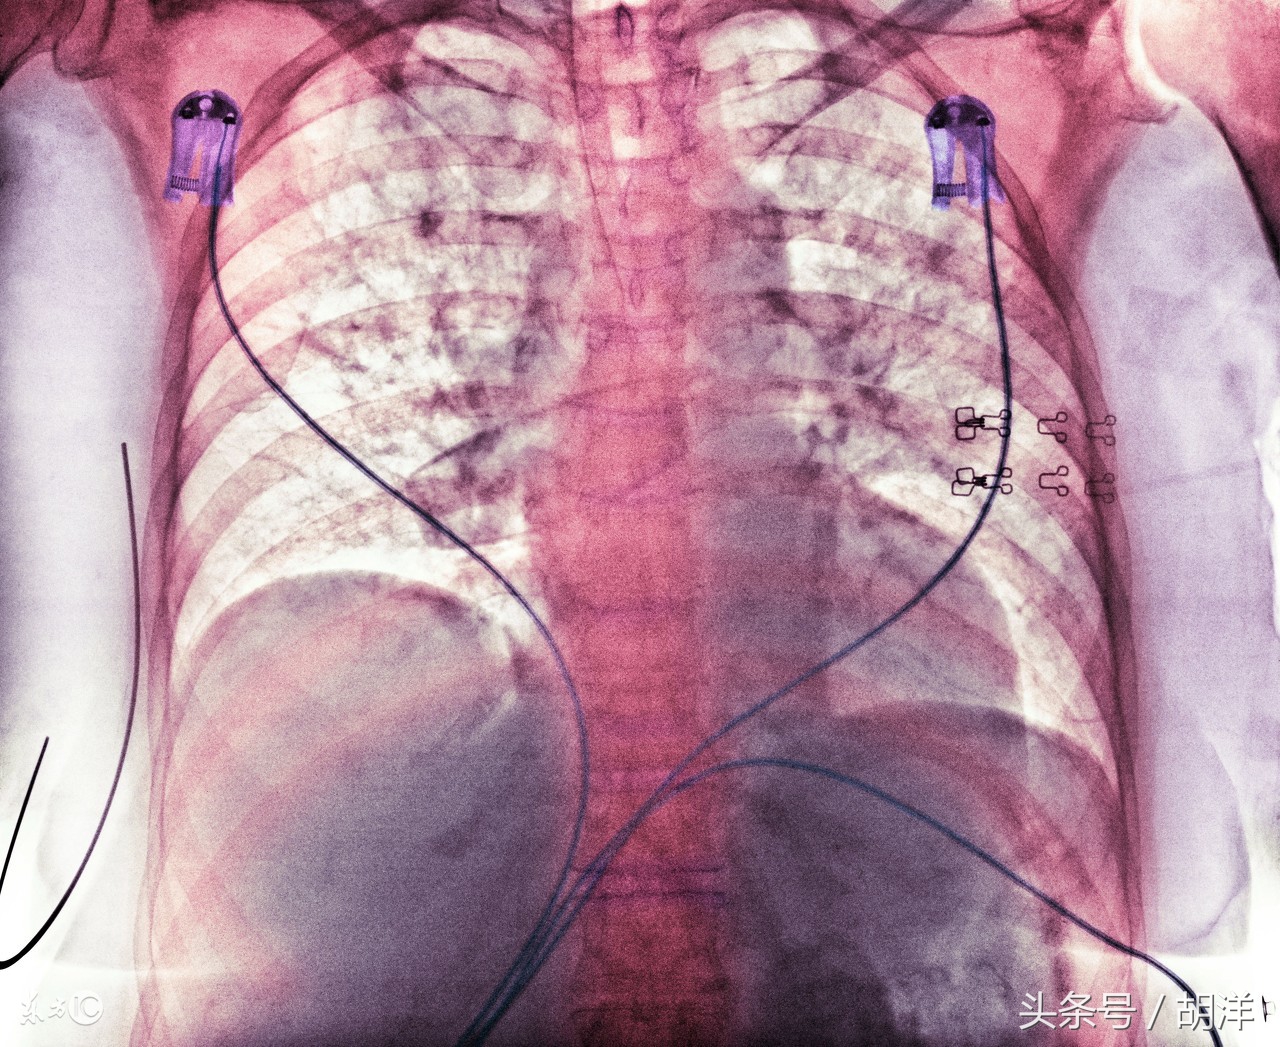

第2是气管镜检查

气管镜检查是用一根可以扭曲的纤维镜,从鼻子进入呼吸道,直接插入肺部检查病灶部位的检查方法。除了可以直观的看到肺内病灶的形态,还可以进行刷检和灌洗。取出来的标本很多,可以检查到相应的病源体,比痰液检查的阳性率更高。